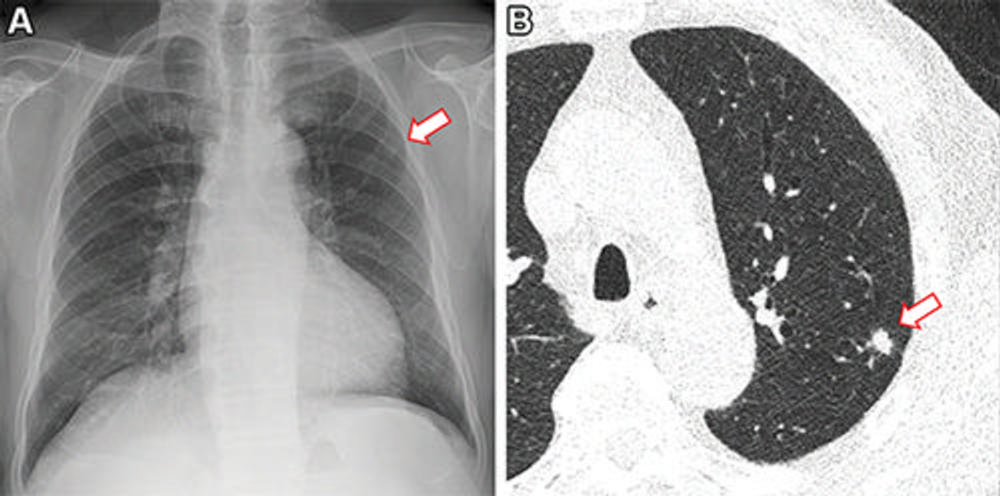

Фотографии и снимки КТ легких без контрастных веществ

Раздел: Визуальный дайджест